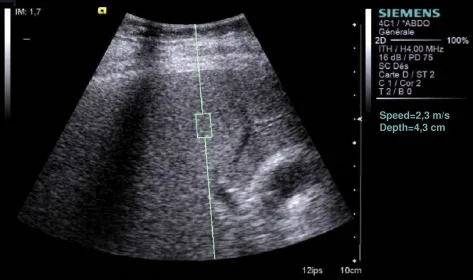

Figure 2. Écran de mesure de la dureté hépatique avec la technique ARFI. La mesure est ponctuelle. La fenêtre de mesure a une taille de 5 x 10 mm. La valeur est donnée en m/s (dans les prochain mois elle sera aussi donnée en KPa).